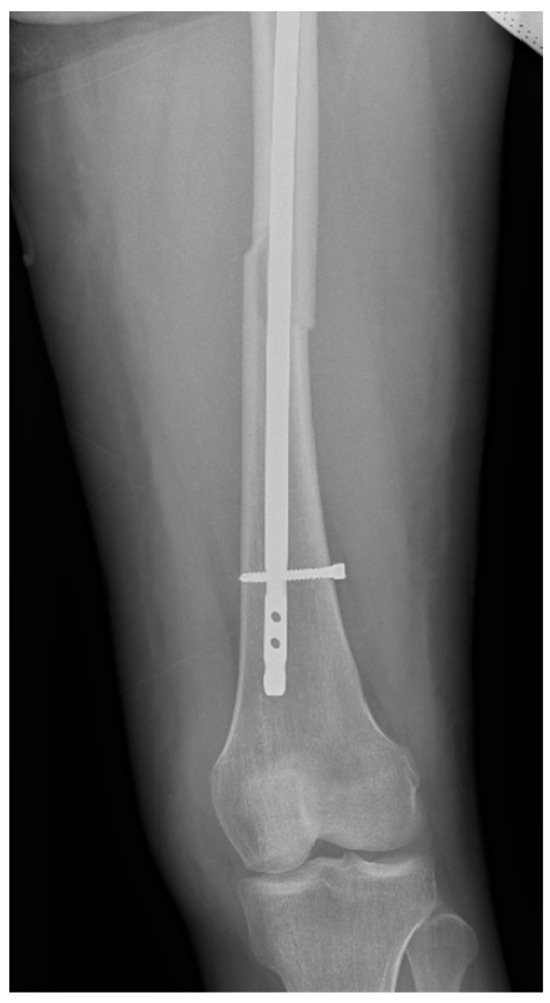

Surgical intervention was performed by a multidisciplinary team: an anesthetist, an obstetrician, a neonatologist, and an orthopedist. She underwent spinal anesthesia utilizing 0.5% bupivacaine, with the extraction of a healthy female baby, weighing 3200 g, with an Apgar score of 9 by C-section and bilateral tubal ligation at the request of the patient, followed by a successful fracture repair under intraoperative C-arm fluoroscopy. The surgical intervention for the fracture of the femur consisted of closed reduction and osteosynthesis with an anterograde intramedullary nail locked proximally and distally with a screw. The postoperative X-ray control revealed good fracture reduction and correct placement of the osteosynthesis material (Figure 2 and Figure 3).

Figure 2.

Postoperative anteroposterior view of the left thigh—proximal pole of the intramedullary anterograde nail fixed with one screw.